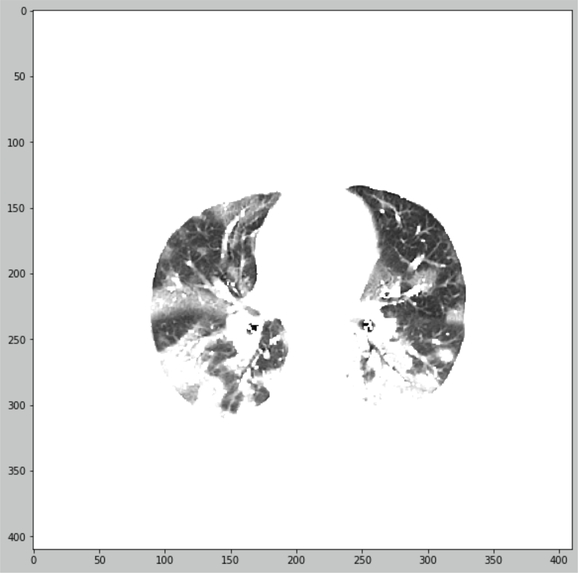

We offer the principle of lungs CT-images quantification with segmentation preprocessing

- Lungs CT-image preprocessed for segmentation

- Lungs masked and segmented